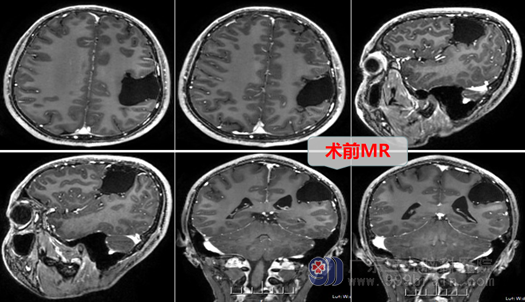

在当地医院做了CT后,医生发现在小丘的左边脑袋(左颞顶部)有一个蛛网膜囊肿,脑袋里长了个囊肿是比较可怕的,这可得赶紧治疗啊!同时,小丘的爸妈还想搞清楚抽搐是不是因为囊肿引起的,为了探究这个真相,经多方打听后他们来到了广东三九脑科医院的外十科就诊。

外十科主任欧阳辉教授解释:自从有了头部CT、MR检查之后,很多人颅内可查出有或大或小的蛛网膜囊肿,但大部分人的囊肿并没有症状,这种没有症状且较小的蛛网膜囊肿是可以观察,不需要急于特殊治疗的。但也有一部分蛛网膜囊肿较大(大于3cm),或是逐渐长大的张力性囊肿,它可以压迫脑组织,引起临床症状,比如颞部较大的蛛网膜囊肿,就容易压迫颞叶,引起癫痫(抽搐)发作,这样的蛛网膜囊肿是需要及时行手术治疗的,小丘的囊肿正是属于这种情况。所以,在欧阳辉主任领导下的神经外十科团队在讨论后决定对小丘的蛛网膜囊肿进行手术治疗。

经过几天的准备,在完善相关检查后,外十科的医护团队为小丘确定了手术方案,为小丘进行左侧颞顶部蛛网膜囊肿壁部分切除+囊肿-脑裂蛛网膜下腔疏通手术。术中在高清显微镜下将囊肿壁大部切除切除,并使囊肿与蛛网膜下腔相通,整个手术非常顺利,术后小丘恢复良好。